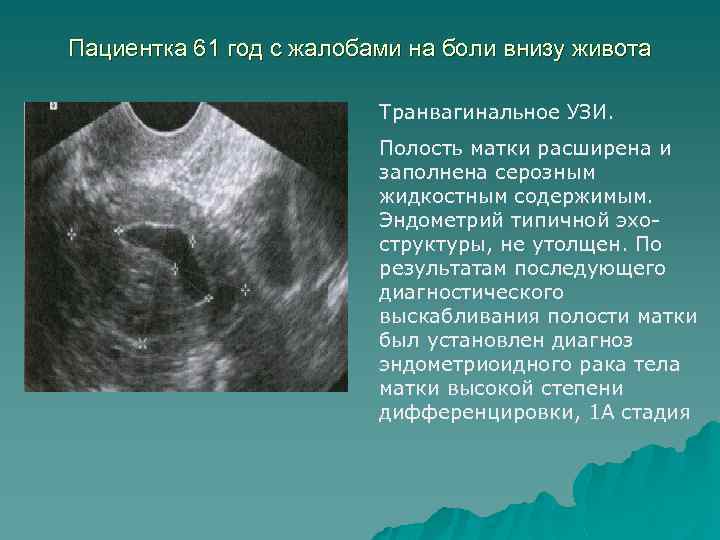

Раздел: Кадры перемен